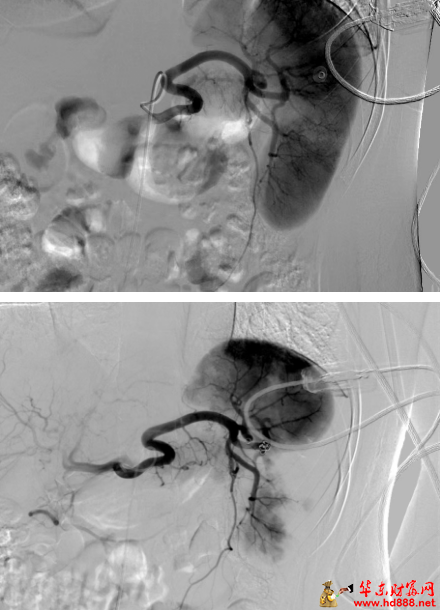

急诊申请介入科团队紧急会诊后,认为有微创保脾的可能! 介入科陈宜新主任解释:“对于符合指征的脾破裂,介入栓塞术是可考虑方案。无需开腹,只需在患者大腿根部进行一个仅有米粒大小的穿刺点,将一根细如发丝的导管,在血管造影机的精准引导下,显示脾动脉损伤的分支血管,然后,注入微小的栓塞材料,就像‘堵住’破裂的水管一样,立即封堵出血血管,同时最大程度保留健康脾组织的血供。” 这是一场在屏幕上进行的“血管内的显微手术”,要求医生拥有极其娴熟的技术和丰富的经验。

在介入手术室里,团队默契配合。屏幕上,血管走向清晰可见。导管到位后,微栓塞材料被缓缓释放,出血征象随即消失,脾脏保住了!整个手术耗时不到一小时。 术后,小雨的血压迅速回升,症状明显缓解。术后第三天转入普通病房,恢复了正常饮食和交流。出院时,介入穿刺点成了一个几乎看不见的小小针眼。